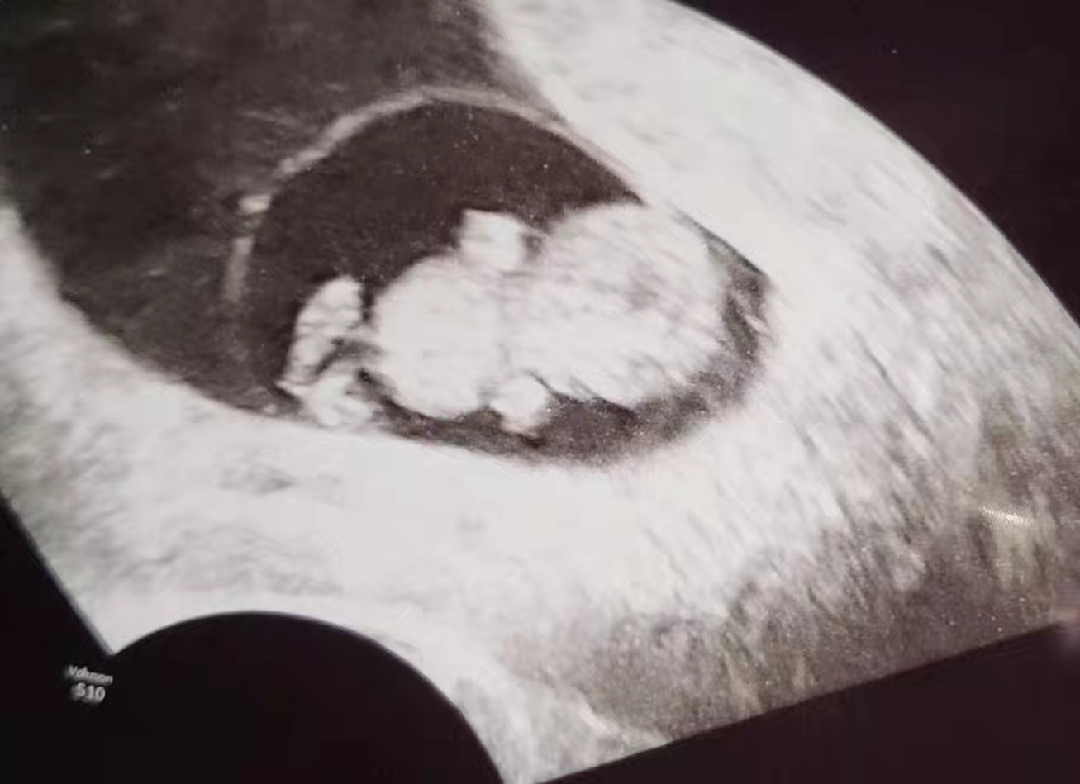

9주 0일 입니당, 2.25cmㅎㅎㅎ🩷 일란성 작은 둥이는 배니싱 트윈으로 아가별로 먼저 보내서 슬펐지만, 무럭무럭 잘 자라고 있는 큰둥이 오늘 정면 보고 있어줘서 고마워🧡 곰돌이 보고 다들 즐거운 금요일 보내세용🫶